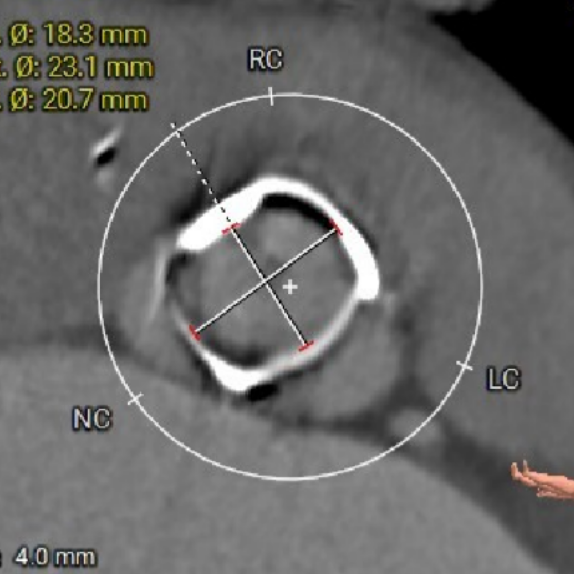

术前CT评估-TAVI viv

瓣架高度

瓣上4mm